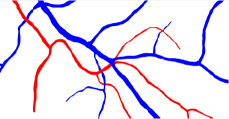

In this paper, we propose a coherence-penalized minimal path model, where the associated minimal paths favour to pass by a vessel that is located in the flatten region of an external feature map. We observe that along a piece of retinal vessel, the values of gray levels vary slowly. More specifically, retinal arteries have lower contrast of gray levels than veins due to the blood materials and imaging modality. In other words, in some extent the arteries and veins are distinguishable in terms of vesselness values. Such an observation can be used to solve the short branches problem that the minimal paths associated to a metric may pass through segments belonging to different vessels as shown in Figs. 1b and 1c. Fig. 1d shows the result from the proposed method, which can avoid such problem. Fig. 1a gives the artery-vein (AV) groundtruth. In this paper, we denote by blue and green dots the source and end points respectively.